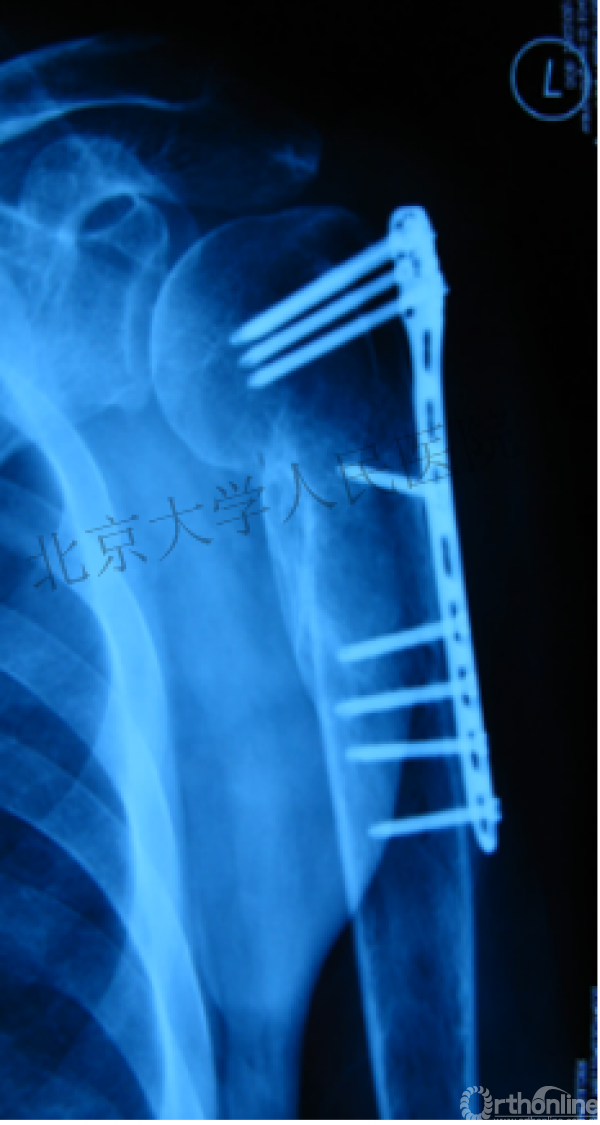

另一个留有遗憾的病例,您的选择?PHN?

临床中的广泛内固定治疗不断地提出思考

结构力学上抗折断能力髓内钉明显强于钢板

三、其实应用肱骨近端髓内钉治疗肱骨近端骨折有时有许多优势。